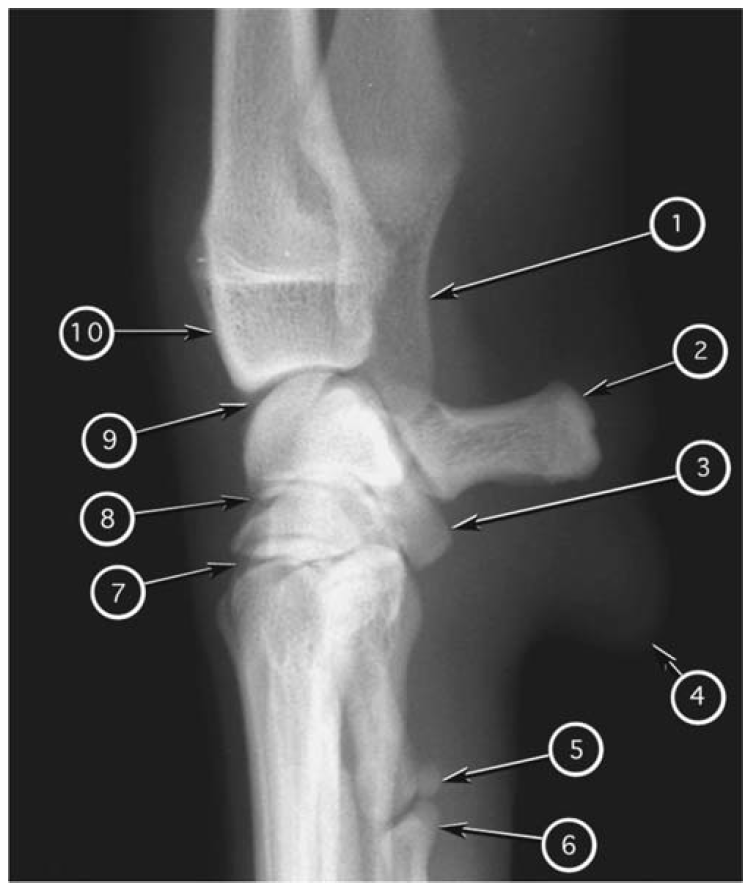

Caudocranial radiograph of canine humerus

What number?

- Clavicle

- Trochlea of humeral condyle

- Capitulum of humeral condyle

- Medial epicondyle of humerus

- Lateral epicondyle of humerus

- Greater tubercle of humerus

- Lesser tubercle of humerus

- Deltoid tuberosity

- Supratrochlear foramen of humerus

- Medial coronoid process of ulna

- Acromion of scapula

A

1. Acromion of scapula

2. Greater tubercle of humerus

3. Deltoid tuberosity

4. Supratrochlear foramen of humerus

5. Lateral epicondyle of humerus

6. Capitulum of humeral condyle

7. Medial coronoid process of ulna

8. Trochlea of humeral condyle

9. Medial epicondyle of humerus

10. Clavicle

11. Lesser tubercle of humerus